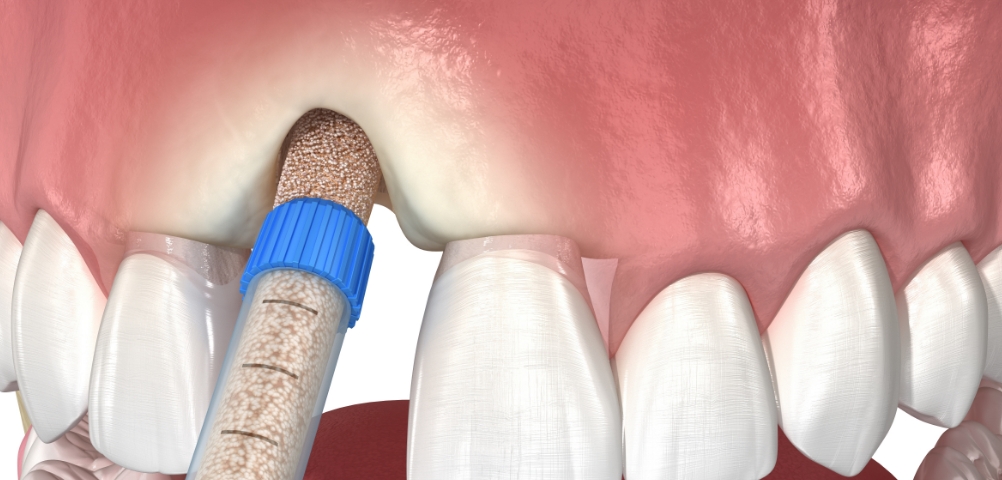

去除蛀牙后,

以树脂材料填补缺损的小区域,

磨牙量少且可呈现与天然牙相近的颜色,

美

观效果佳

当蛀牙范围较大或扩散至牙齿侧

面时适用,

因嵌体为精密制作并贴合牙体,

具有良好的密合性,

不易脱落的优点。